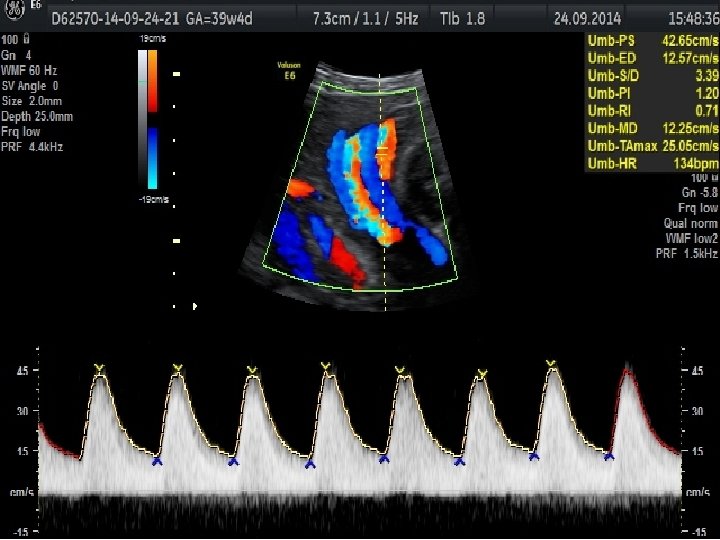

FETAL BÜYÜME BOZUKLUKLARINDA TAKİP VE DOĞUM • Günlük pratikte gelişme gerilikli fetusların takibi, ultrasonografi ile fetal biyometri ve amniyotik sıvı miktarının belirli aralıklarla ölçülmesi ile ve nonstres test veya biyofizik profil gibi antepartum fetal iyilik hali testleri ile yapılmaktadır. • Plasental yetmezliğe bağlı gelişen fetal gelişme geriliğinde standart fetal izlem ile birlikte fetal arterial/venöz dolaşımın Doppler değerlendirmesinin nonstres test ve biyofizik profili ile birlikte kullanımının daha iyi fetal sonuçlar ile ilişkili olduğu gösterilmiştir.

Obstetrik Doppler Ultrasonografi • Umblikal arter Doppler’i en yaygın olarak kullanılan fetal Doppler değerlendirmesidir ve en fazla kullanılan Doppler parametresidir. • Orta serberal arter Doppler • Umblikal arter Doppler değerlendirmesinde direnç artışı, diyastol sonu akımda kayıp veya ters dönme saptanması , artmış perinatal mortalite hızı ile ilişkili olmakla birlikte fetal gelişme geriliği olgularında doğum zamanlamasının belirlenmesini de etkilemektedir.

• Duktus venosus Doppler’inin kötü perinatal sonuçları tahmin etmedeki katkısı sınırlı olmakla birlikte yenidoğan sonuçlarını öngörmede en önemli kardiyovasküler parametre duktus venosus Doppler’idir.